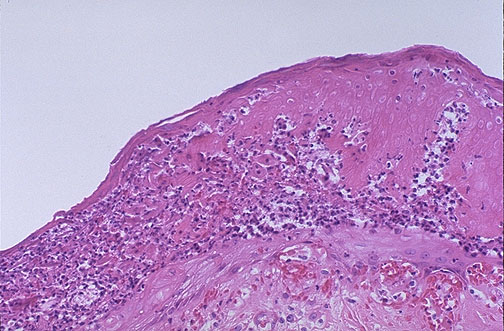

| Purpura fulminans, with extensive dermal vascular thrombosis followed by peripheral gangrene, can be due to sepsis (often with streptococcal organisms), coagulopathy (DIC or protein C or S deficiency), and warfarin therapy. Seen here is extensive skin necrosis with inflammation. |